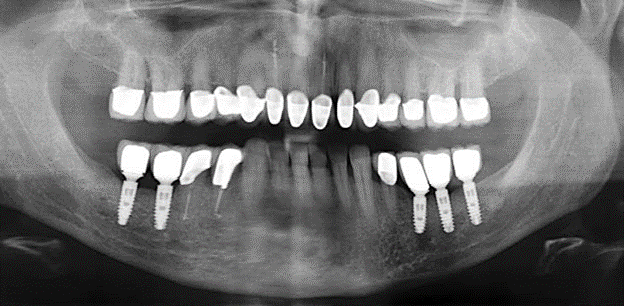

Fig. 1: Panoramic radiograph of initial situation in 2004.

A 52-year-old patient presented in our clinic for the first time in 2004 following tooth loss in the third quadrant, expressing a desire for a new prosthetic restoration. Periodontal and radiological diagnostics revealed the need for extensive periodontological treatment. In addition, teeth 48, 28 and 27 were attributed a very poor prognosis and were subsequently extracted (Fig. 1). Following the successfully completed, systematic periodontological treatment, a fixed dental implant was inserted with the introduction of five implants in tooth regions 35, 36, 37, 46 and 47. Prosthetic treatment of the natural teeth was effected with veneered zirconium dioxide ceramic crowns; the implants were composed of two-piece, individual zirconium dioxide abutments and similarly veneered crowns made of a zirconium dioxide ceramic (Cercon base colored, Dentsply Sirona Lab). Definitive insertion of the prosthetic restoration occurred in 2005.